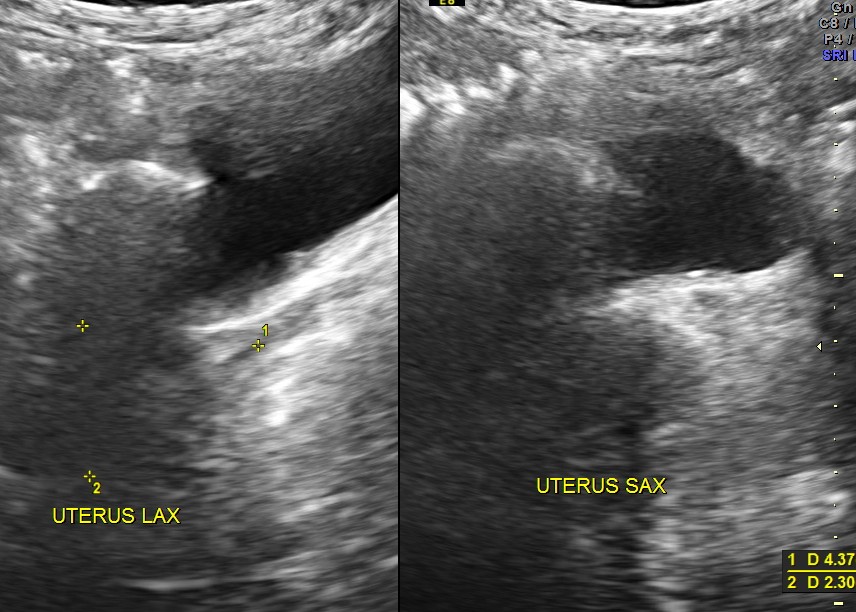

The uterus and ovaries were shrunk.